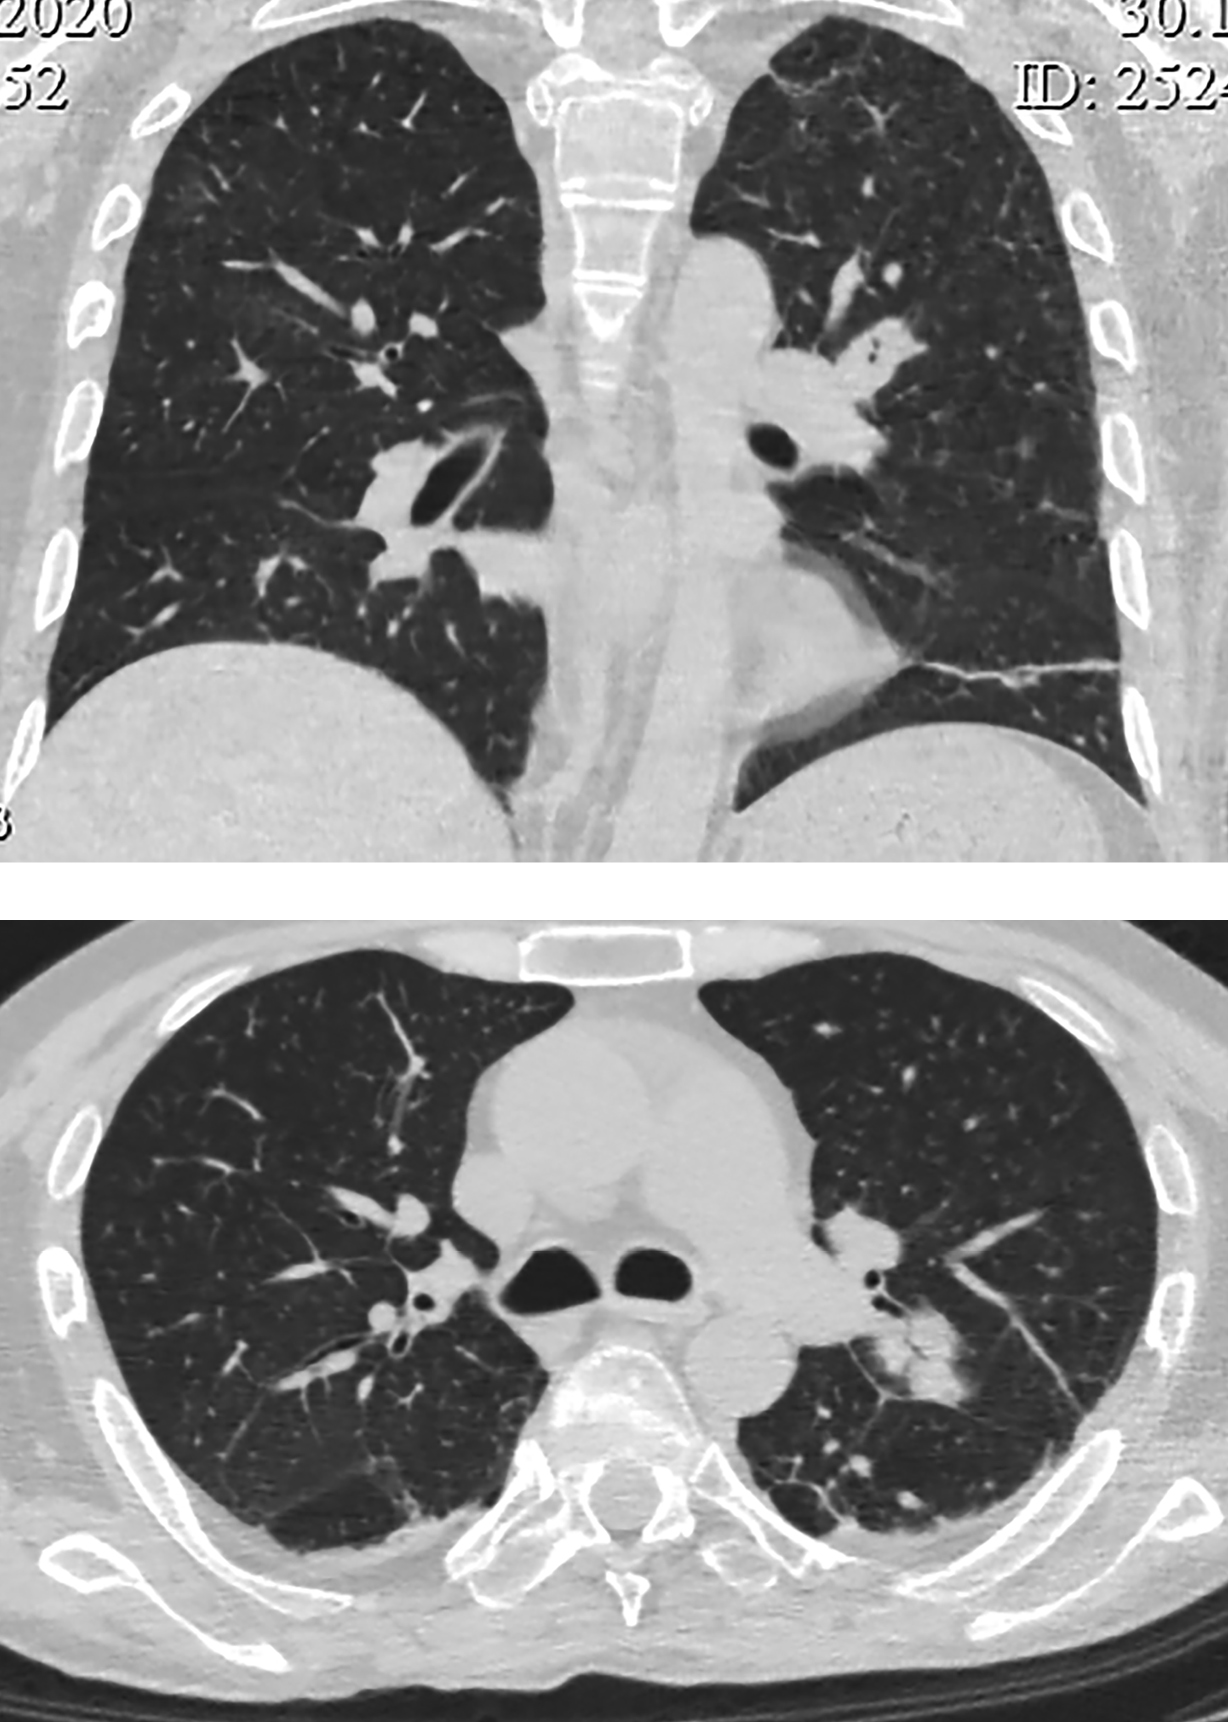

Локальное уплотнение легочной ткани было расценено либо как метастаз опухоли ЩЖ, либо как первичная опухоль легкого. При КТ брюшной полости новообразований не выявлено. Визуализированы признаки пареза кишечника (рис. 4), диффузная гиперплазия обоих надпочечников — толщина правого увеличена до 1,4 см, левого — до 1,6 см (рис. 5). При КТ головного мозга выявлены признаки выраженной атрофии коркового вещества. Область турецкого седла не изменена.

Рисунок 4. КТ брюшной полости: парез кишечника.

Рисунок 5. КТ брюшной полости: диффузно-гиперплазированные надпочечники: правый — до 1,4 см, левый до — 1,6 см.